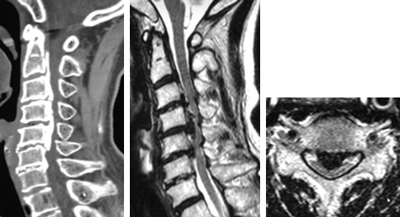

頚椎後縦靱帯骨化症のCT、MRI。骨化によって脊髄が高度に圧迫されています。